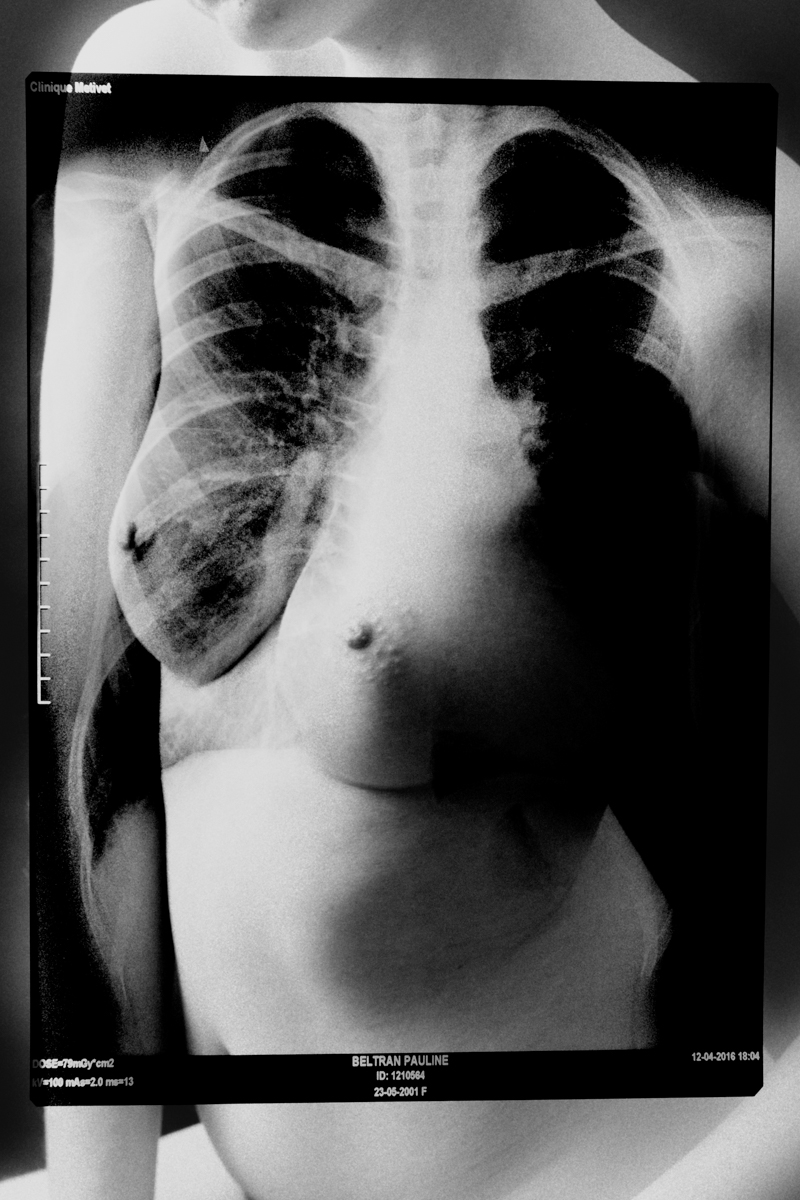

SURFACES SENSIBLES — À la frontière de l'autoportrait, "Surfaces sensibles" retranscrit une partie de ma réalité et brouille les limites entre l'intime anatomique et l'émotionnel.

La science produit les images les plus concrètes et les plus neutres pour illustrer les affects. Pourtant, par leur froideur et leur distance, elles sont les moins aptes à témoigner des émotions. Chaque radiographie, scanner, IRM correspond à une douleur ou à un mal-être spécifique.

Depuis peu, ces images ne sont plus seulement des réminiscences de douleurs passées, mais également des matériaux bruts inspirants pour ma pratique photographique. À partir des radios originelles, j'ai utilisé plusieurs techniques telles que la superposition et le tirage argentique dans le but de me rapprocher d'une perception alternative de ce corps irradié.